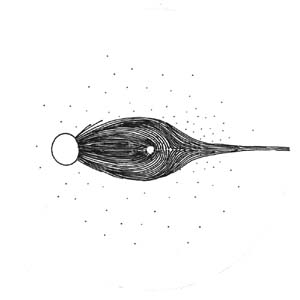

Lokalizovaný výpadek nervových vláken byl popsán poprvé teprve roku 1973 Hoytem. Je vějířovitého tvaru, připomínající ocas komety. Vyskytuje se u 20% glaukomů, není však pro glaukom specifický (drůzy, chorioretinální jizvy, dlouho trvající edém disku, pozánětlivá atrofie). Není u zdravých očí.